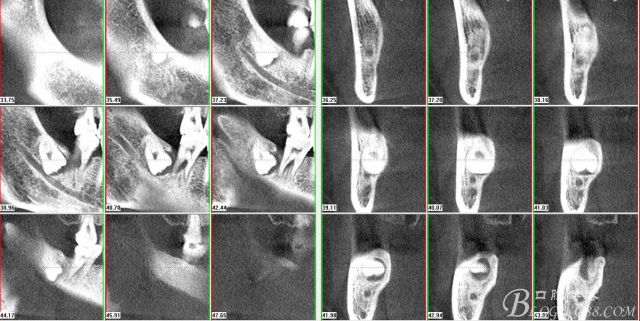

二、術前CBCT影像:

圖1. 47牙冠的近中面緊鄰下頜神經管

圖2.判斷47牙根是否吸收

圖3.通過矢狀面和冠狀面來判斷48與下頜管及47的關系

圖4.水平方向48與47之間的關系